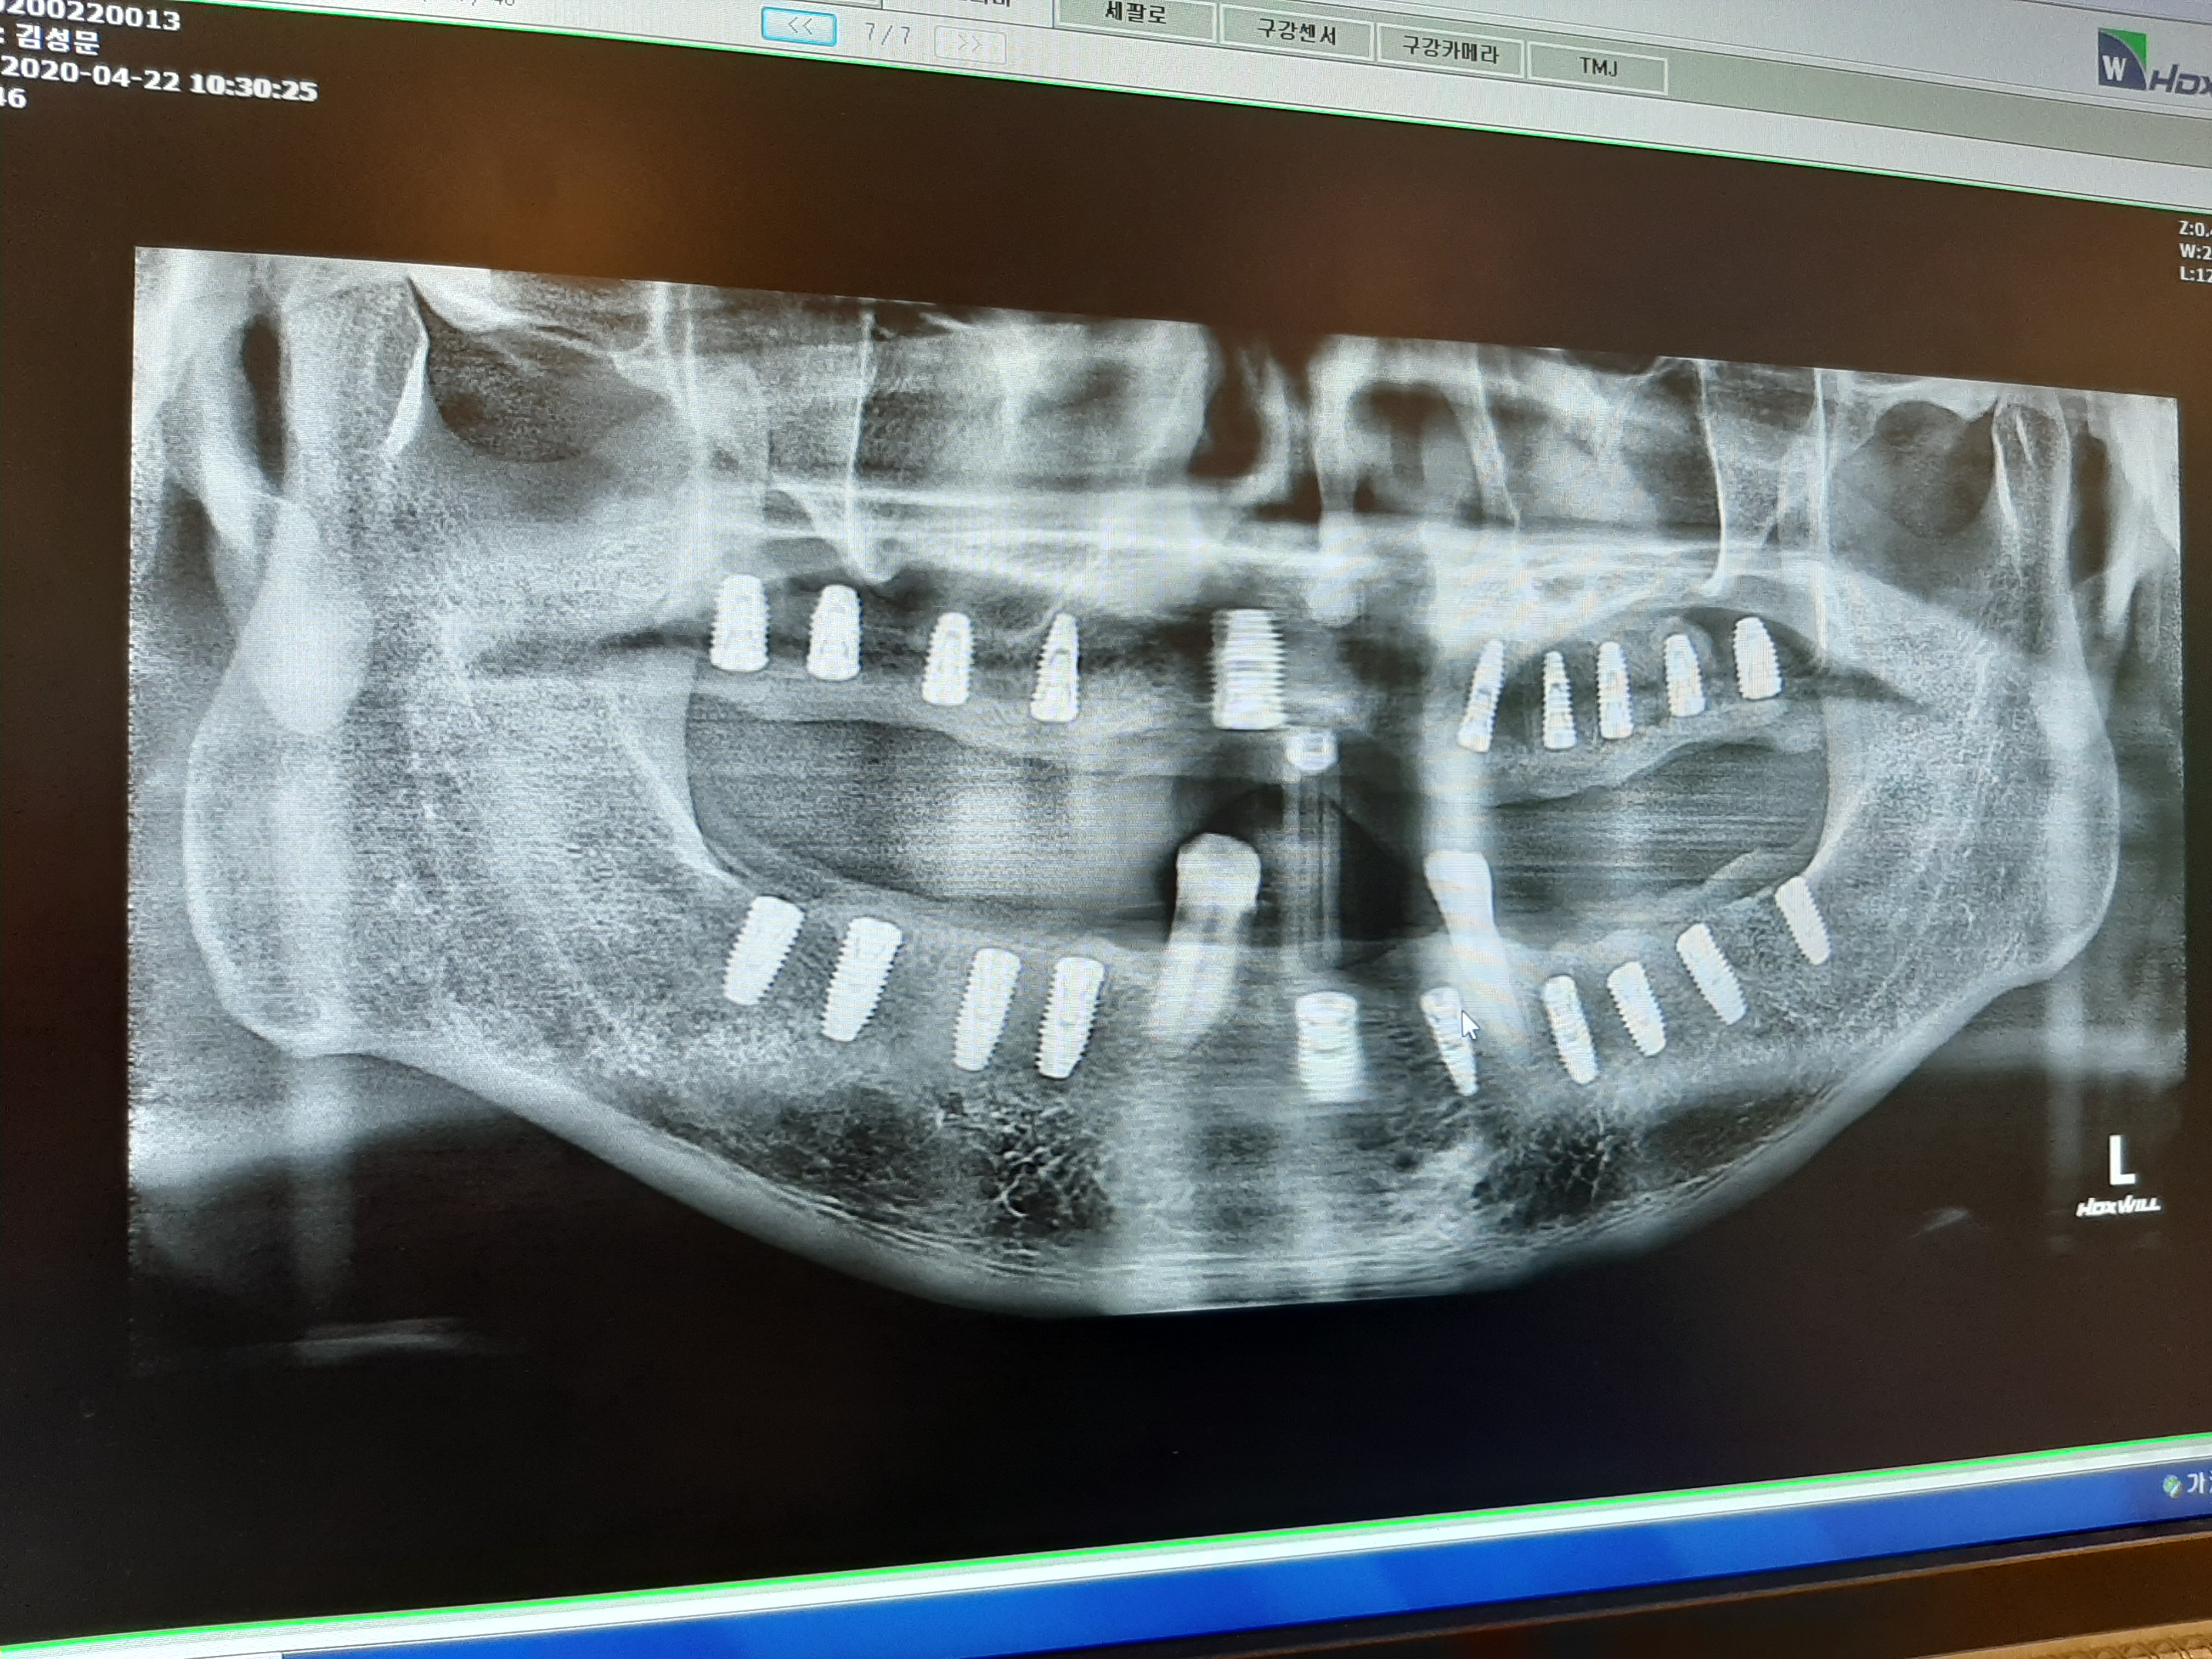

앞니는 까다로운 곳이다. 심미성에 많은 신경을 써야 할 뿐 아니라 형태 등 다양한 부분을 두루두루 고려해야 한다. 치아가 빠지고 나면 골 흡수가 시작된다고 하는데 앞니는 다른 곳 보다 골이 얇은 편이라 어금니나 다른 부분에 비해 흡수가 빠르게 진행될 수 있다고 하여 조금은 걱정이 되었다. 뼈이식은 하지만 뼈가 너무 없어서 또 다른 조치를 해야 하는 것은 아닌지 조금은 걱정이 되었다. 다른 치아들도 걱정이 되었고 어금니는 위아래 양쪽이 없었기 때문에 혹시 뼈이식 이외에 더 해야하는 것이 있는 것은 아닌지 추가로 돈을 더 내야 하는 것은 아닌지 조금은 걱정이 되었는데 무사히 뼈 이식으로 끝났다. 이번에도 의사 선생님이 앞니에 뼈가 별로 없다고 하셨다고 하길래 또 뭔가 조치를 취해야 하는 것은 아닌지 걱정이 되었지만 앞니에 뼈가 많은 부분으로 임플란트 식립을 했다고 한다.

그리고 앞니는 빠진 상태로 반년 정도 지났기 때문에 혹시 임플란트 식립 할 때 뿌리가 드러나는 경우도 있다고 하길래 내심 걱정이 되었다. 앞니는 사람들과 만날 때 말할 때 제일 먼저 보이는 부분이고 웃을 때 치아가 가지런하고 좋아야 할 텐데 걱정스럽기도 했다. 다행히 뼈이식만 하고 임플란트 2개를 식립 했다.

이제 모든 치아를 발치하고 아래 송곳니 2개만 남아 있다. 2주 후 실밥을 뽑고 임시틀니를 할 건데 그때 위아래 아무 치아도 없는 것보다 아랫니 송곳니가 있으면 훨씬 좋다고 하시고 또한 송곳니의 상태가 조금은 괜찮아서 완전히 치아를 다 하기 전 까지는 써보기로 했다. 그리고 임시틀니를 되도록이면 하면 안 된다고 하였다. 미관상 사람들 만날 때만 사용하고 나머지는 빼고 있어야 빨리 살이 차오르고 좋아진다고 하였다.